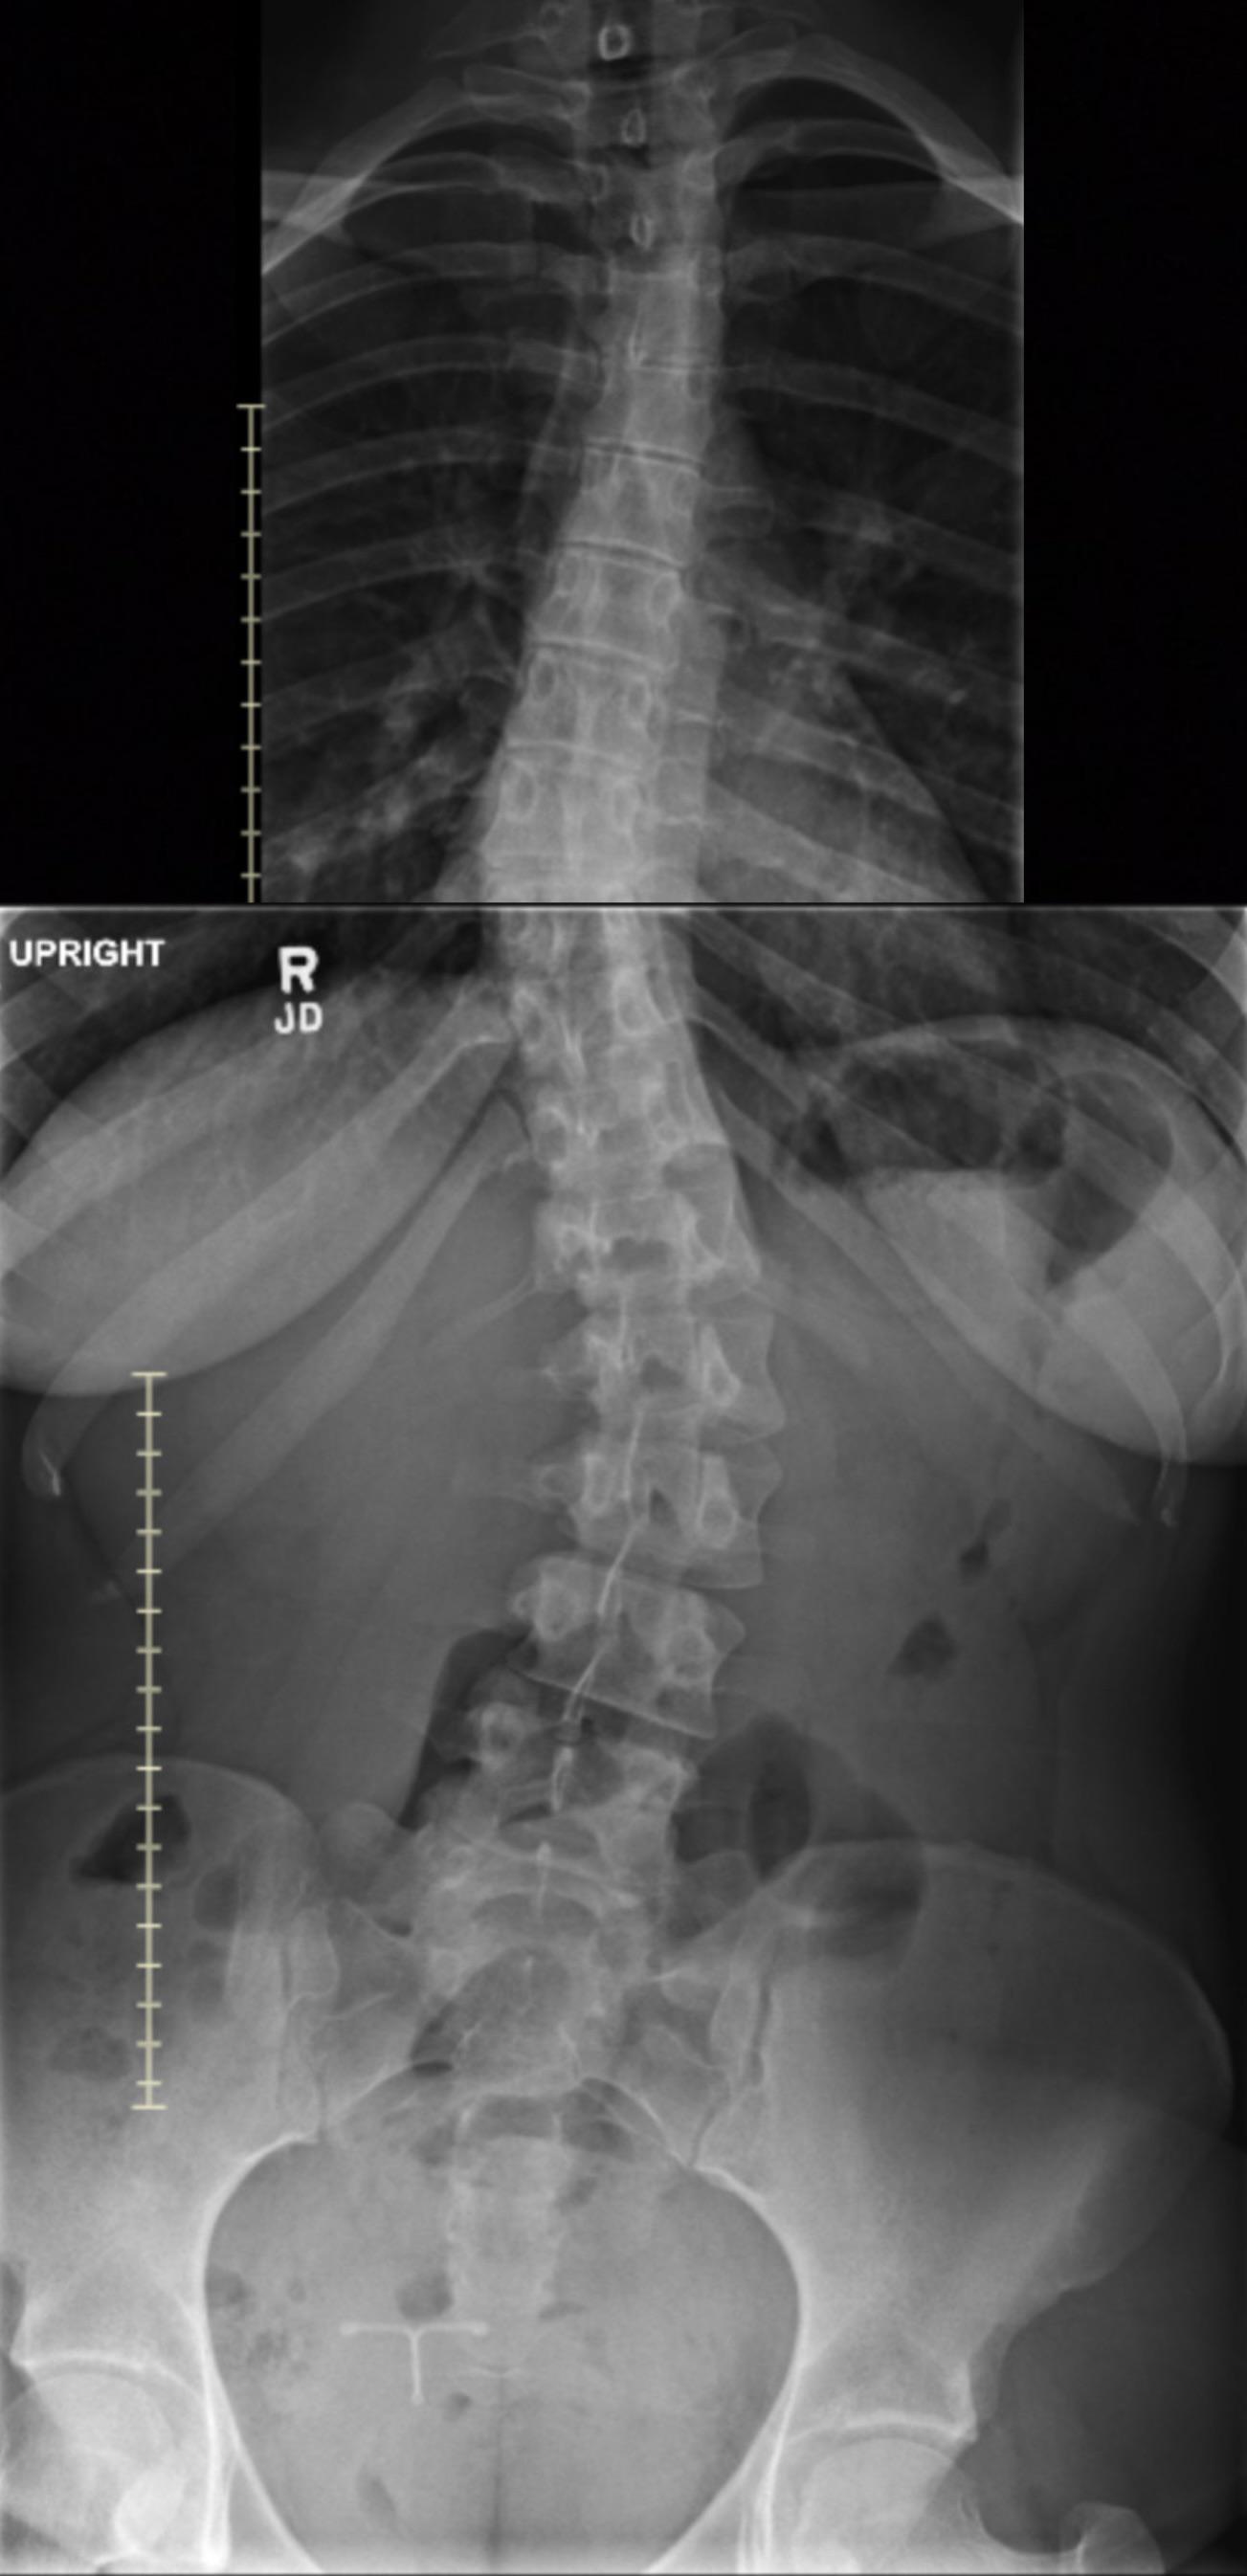

Submitted by LaisyDucky t3_119lnjt in mildlyinteresting